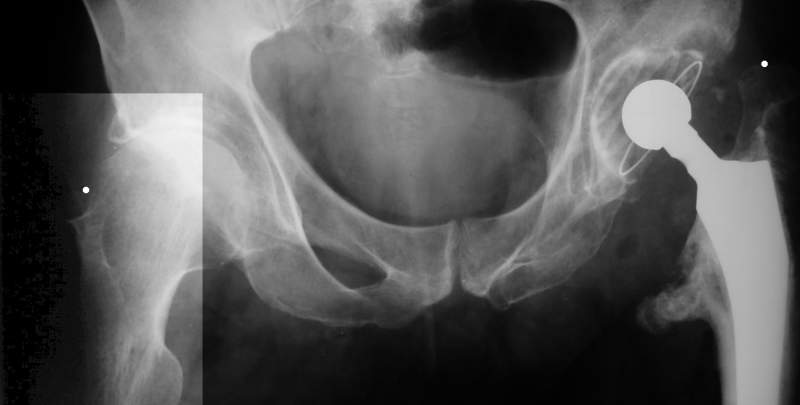

AV> опираясь на стул. На ногу не наступает. Укорочение 8 см. Иногда

А за счет чего такое укорочение? По снимку не видно соответствующего дефекта. Ну плюс приводящая контрактура - но все равно как-то уж больно много. Может, сделать снимки и таза обзорный с обоими проксимальными отделами бедра, и коенный суставов с приложенной линейкой какой?

Судя по снимку, максимум истинное укорочение около 4 см, что может быть коррегировано интраоперационно. Вопрос в другом: куда ставить ацетабулярный компонент в истинную или во вновь сформированную ( впадина диспластичная).

Невозможно не согласиться с Анатолием, чтобы заниматься адекватным планированием как минимум прямая проекция таза должна быть сделана, как

максимум для оценки состояния мышц( насколько реально возможно низвести бедро) прямая проекция таза с тракцией за больную ногу.

The X ray that you provided does not show 8 cm of shortening. Perhaps you could send one showing the whole pelvis and proximal femurs.

I agree with Dr Eid's comments. The origin of the 8 cm leg length difference is a puzzle. Is this a clinical measurement? In that case contracture of the joint might affect the measurement. Can we see an AP pelvis to include both hip joints (including a calibration object with a known length) so that the difference in leg lengths that can be ascribed to the hip deformity and bony reabsorption can be measured. This sort of xray will help with templating for the TJR also. I would be very tempted to do a one stage procedure and accept some shortening. Shoe lifts should take care of a 3-4 cm difference.

До травмы проблем с ногой не было. Укорочения, болей и т.п. не отмечал. Сегодня перемерял укорочение - меньше 7 см намерять не

получается :)

По уровню малых вертелов (с учетом рентгеновского увеличения) получается 5 см. Клинически ногу низвести путем тракции невозможно. Из движений - сгибание до 40*, остальные движения "символические".

Ортопедическое укорочение пострадавшей ноги может быть и 7, и 10 см. за счет контрактур в тазобедренном суставе, а вот истинное укорочение, судя по представленным рентгенограммам, вряд ли больше 4 см.